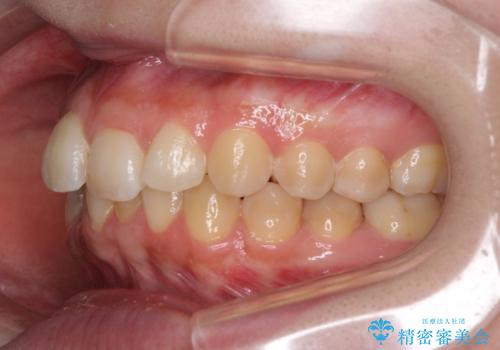

前歯のデコボコをインビザライン矯正で綺麗に改善

- 上下前歯のデコボコを気にして来院された患者様です。

全体的に叢生は軽度であったため、インビザラインにて矯正治療を行うこととしました。

舌の突出癖改善がうまくいかず、途中で舌小帯の切除を行いました。

気になる段差を納得いくまで改善させたため、治療期間は長くなりましたが、綺麗な仕上がりとなりました。